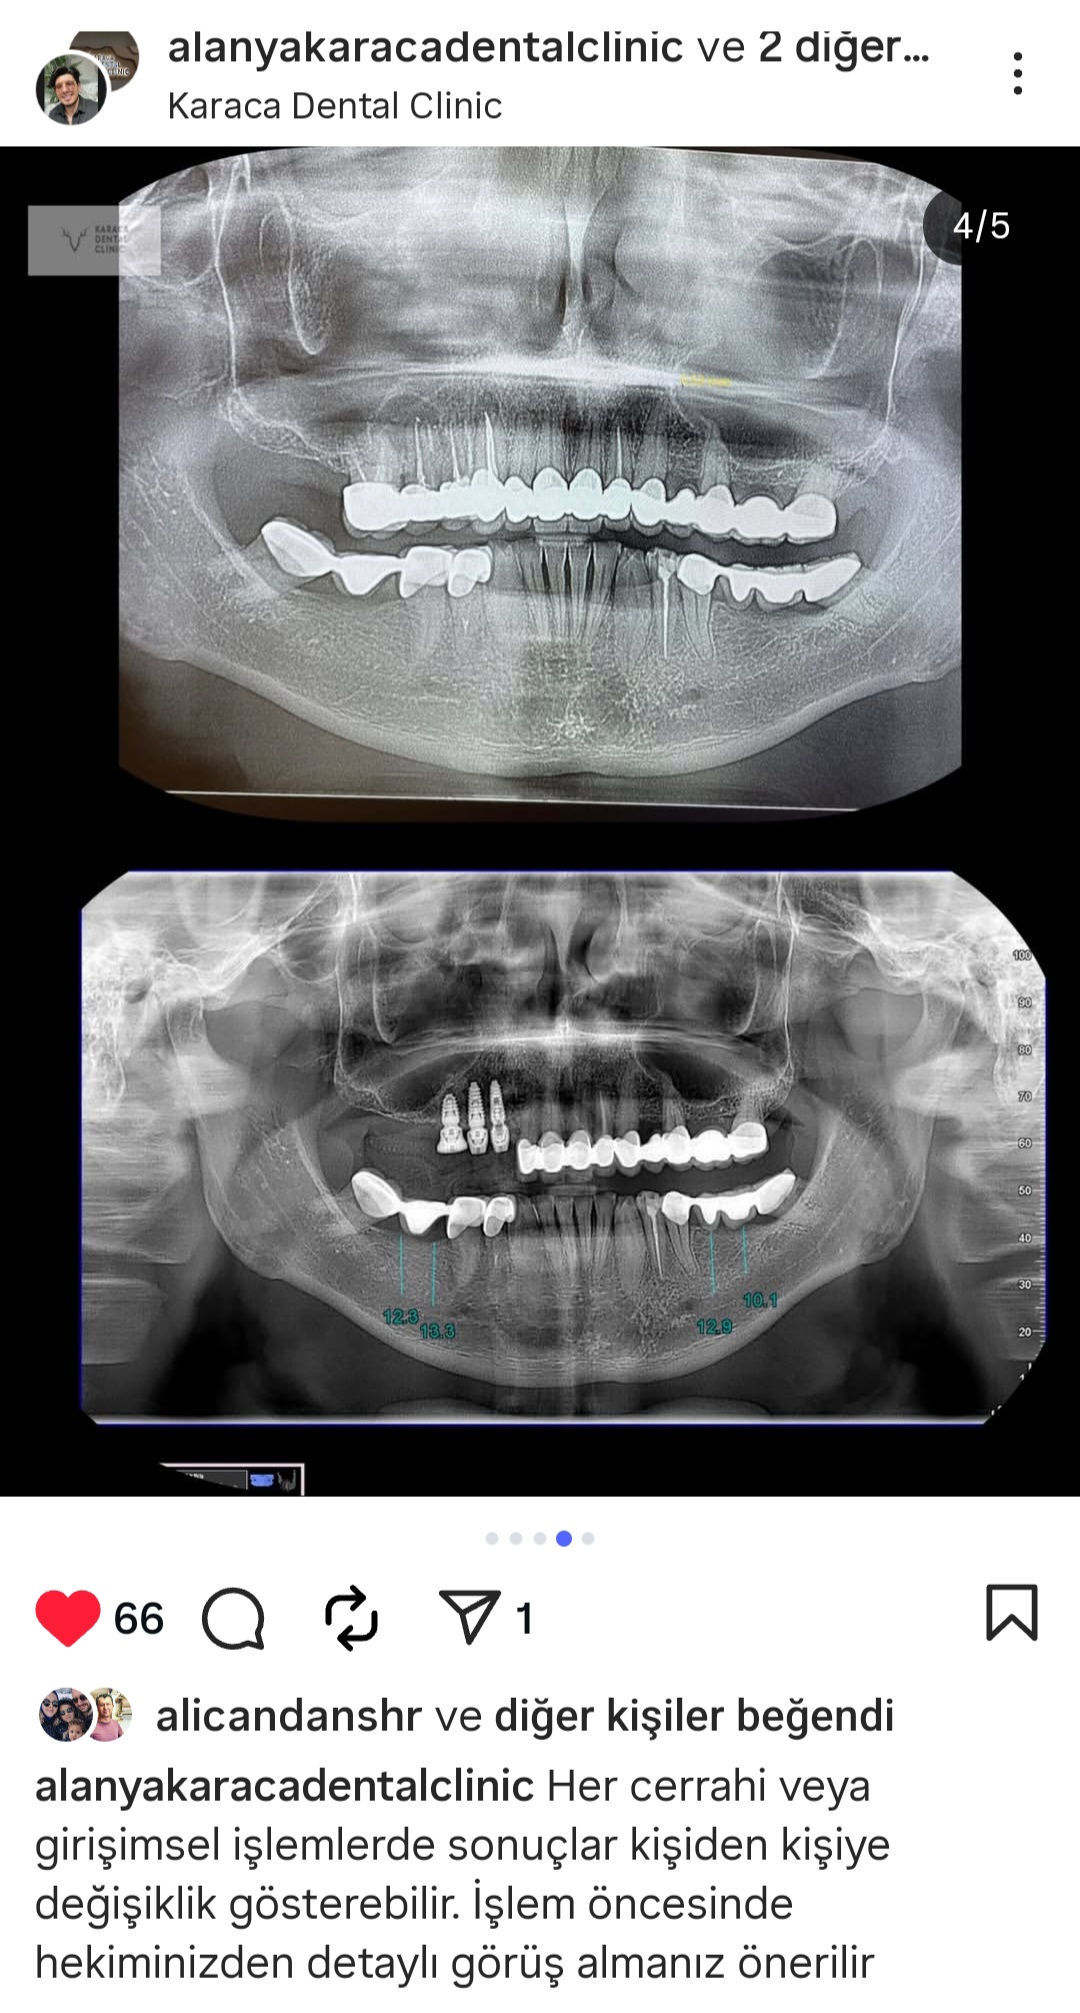

- Diş Dolgusu Kanal Tedavisi İmplant Tedavisi Çocuk Diş Hekimliği (Pedodonti) Lamina Kron Kaplama Zirkonyum Kron Kaplama Estetik Dolgu Estetik Gülüş Tasarımı Hollywood Gülüşü Diş Taşı Temizliği Air Flow Diş Temizleme Diş Beyazlatma Diş Çekimi Gece Plağı Dijital Diş Hekimliği 7/24 Diş Kliniği Hizmeti Acil Diş Kliniği Hizmeti Nöbetçi Diş Kliniği Hizmeti # HİZMETLERİMİZ #